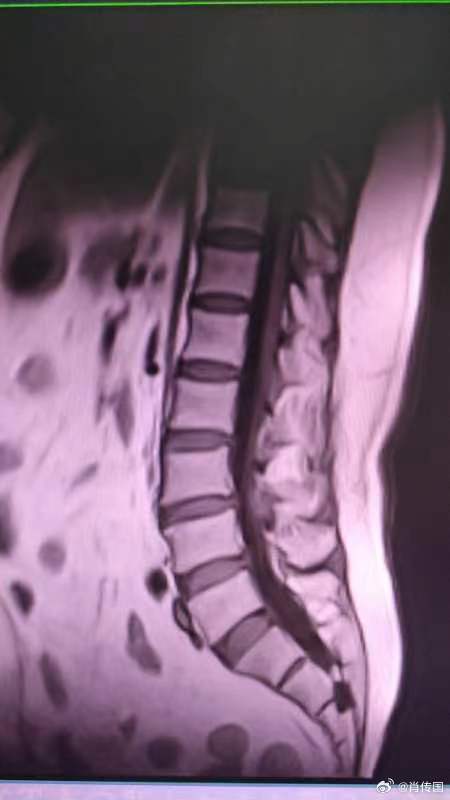

对任何病,医生即使再有把握,也决不会拍胸脯打包票100 %治好。可近日面对一个孝顺儿媳,我𨚫用林彪元帅的方式打包票了。深圳市南山区医院转来一位7 0岁女性患者,尿道口会阴部膀胱区刺痛难忍,不到20分钟就要上厕所,膀胱容量50多毫升,近10年,在外院多方治疗无效,痛苦不堪。陪患者来的是其儿媳,护士长。她说去年底还花了10几万置入骶神经刺激器,仍完全无效。我笑着说去年深圳医护均大幅减薪,不但无年终奖,还被追回头年奖金,你挺有钱吗!她说婆婆太痛苦,再缺钱也得治啊。面对这孝顺儿媳、同行,挺感动,一时间林副主席附体,立即告诉婆媳俩:虽然还没详细检查,但作为同行,我就直接了当了,这种情况我们非常有把握治好,而且手术效果会"立竿见影”。婆媳俩非常高兴,虽仍将信将疑,但看我这么德高望重又不像是开玩笑[呲牙]。其实这种情况主要就是支配膀胱会阴的神经束或神经根受压所致,换个思路可以让问题简单化:这和坐骨神经疼是一个道理,神经受压位置不同罢了。检查结果出来果然不出我之所料:1,脊髓磁共振检查显示隐性脊柱裂,骶管囊肿,异常增厚硬化的黄韧带严重压迫硬膜腔终端骶神经束。2,尿动力学仅能灌入60 ml,逼尿肌过度频繁收缩,远超普通的OAB(唯一有肯定疗效的骶神经刺激器置入适应症),轻度DESD。行骶管探查,囊肿切除,黄韧带切除。(这种神经源性膀胱只要骶神经尚未完全压榨脱失萎缩,绝大部分不需肖氏手术)术后麻醉一醒,尿道、会阴小腹的刺痛消失,令将导尿管夾闭,待病人有尿意时再放开,每次尿量300多毫升。完美的“立杆见影”了。